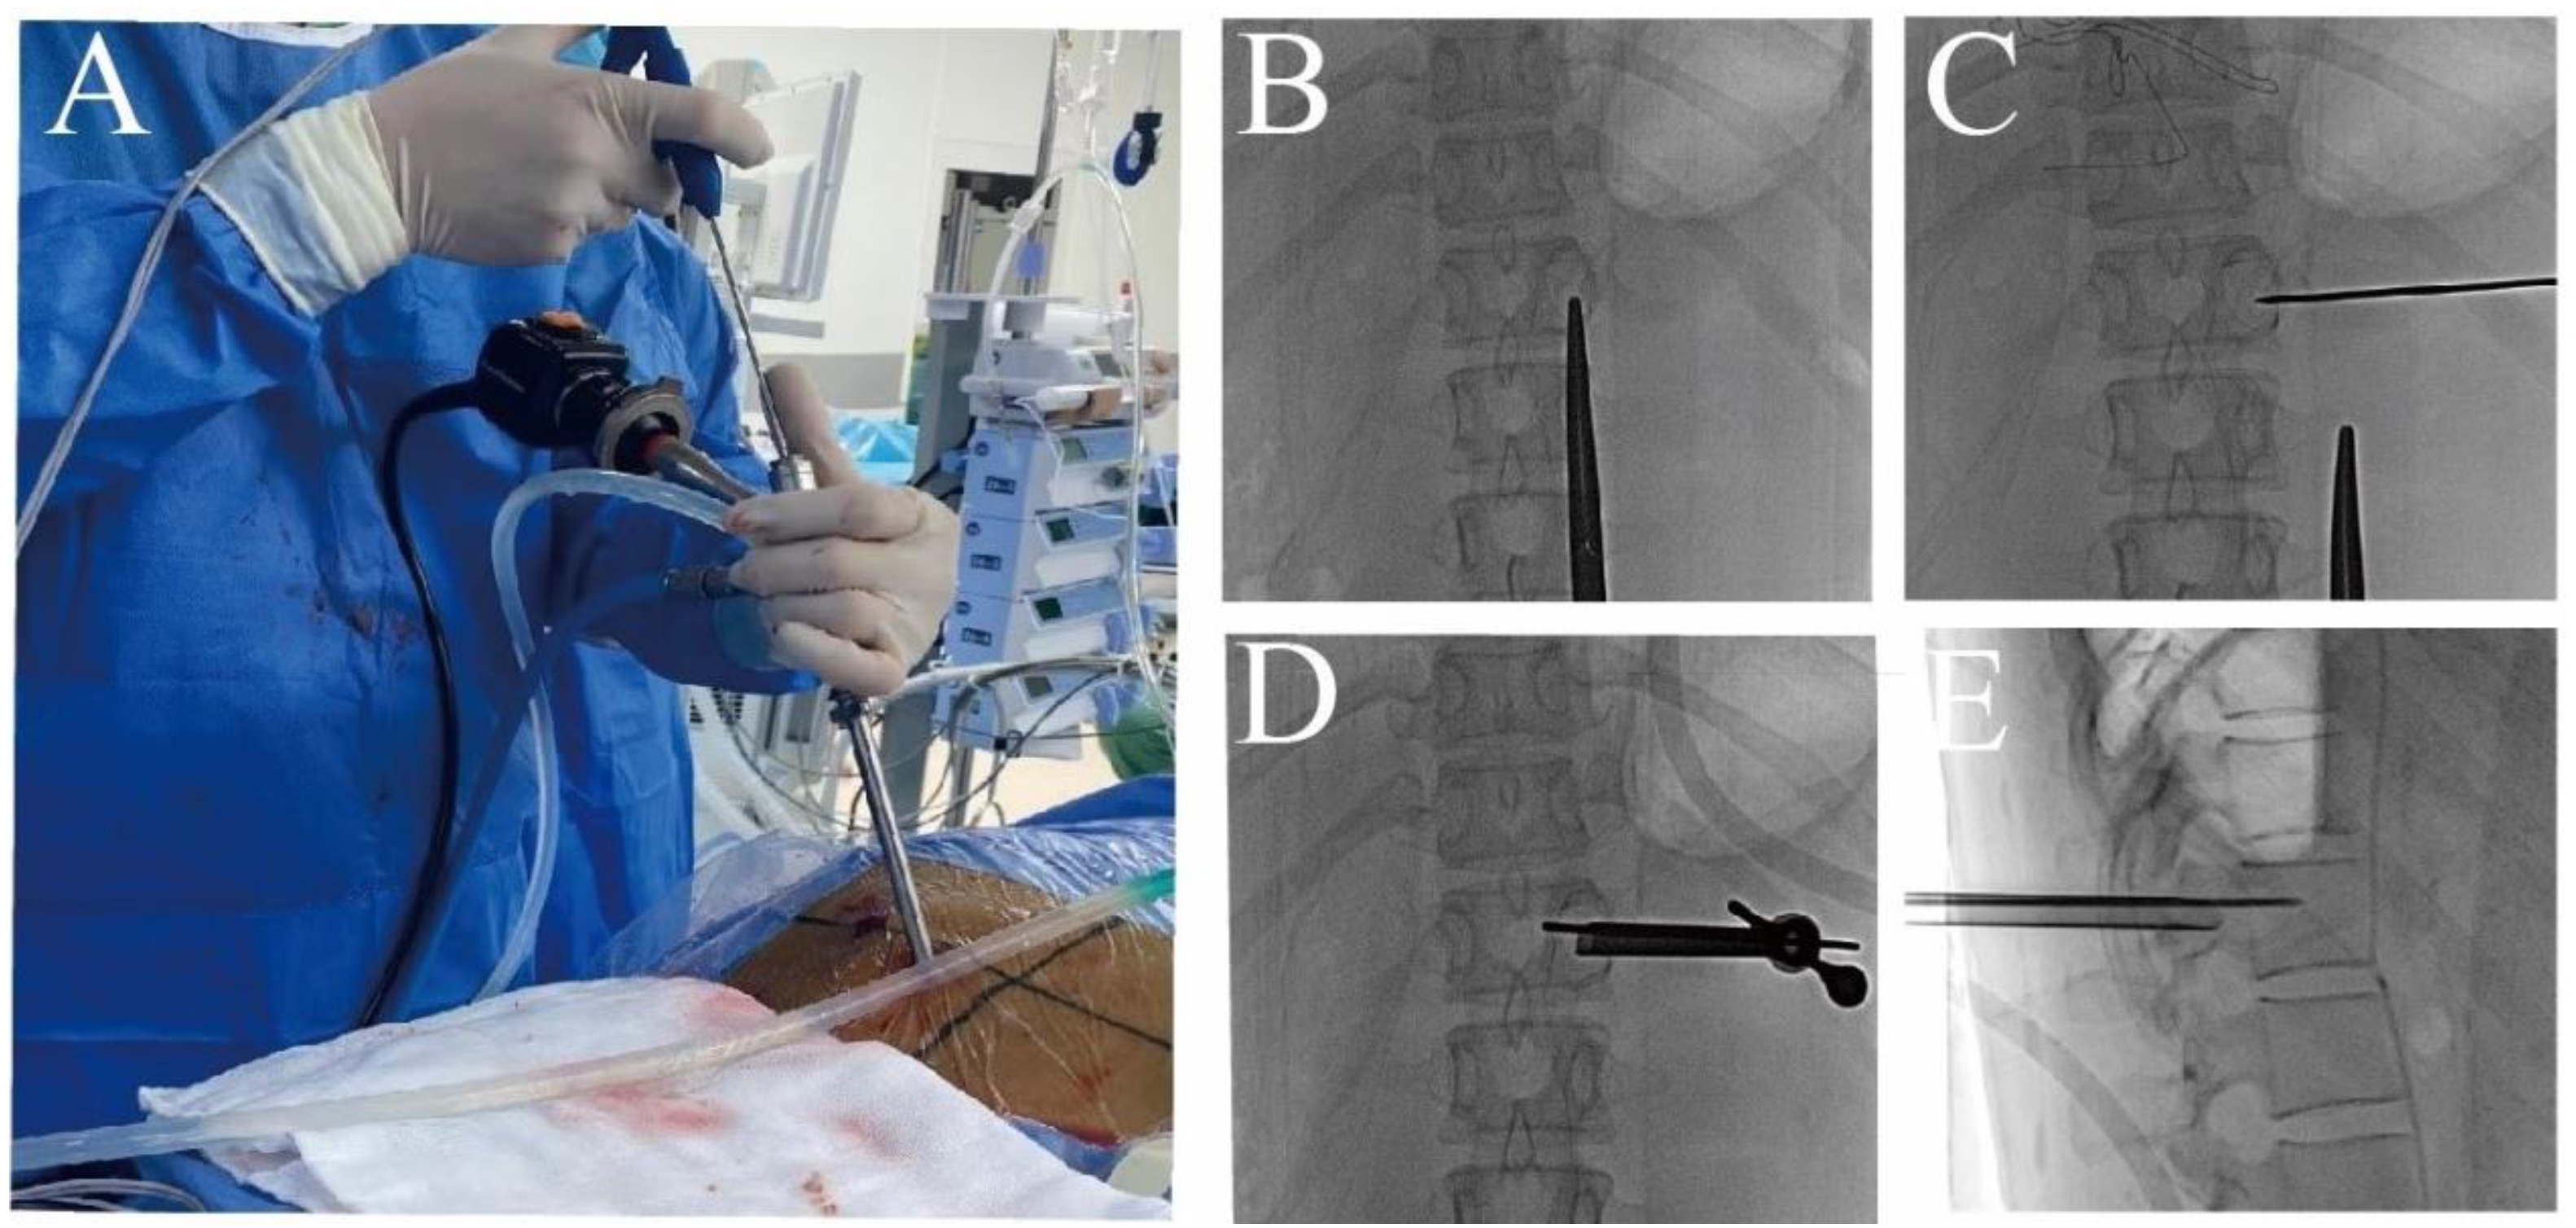

2.2. Surgical Technique

2.2.2. Surgical Procedure